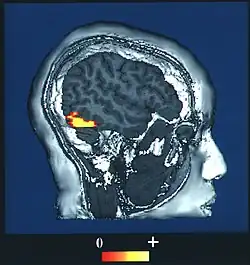

El "área de rostro" FFA está localizada dentro de la red neuronal llamada corriente ventral ubicada en la superficie ventral del lóbulo temporal en la región lateral del giro fusiforme.

El área FFA es lateral y externa al "área de lugar" situada en el parahipocampo. La FFA muestra una cierta lateralización, usualmente siendo más grande en el hemisferio derecho.